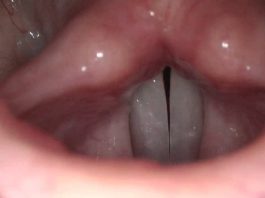

La importancia de calentar la voz